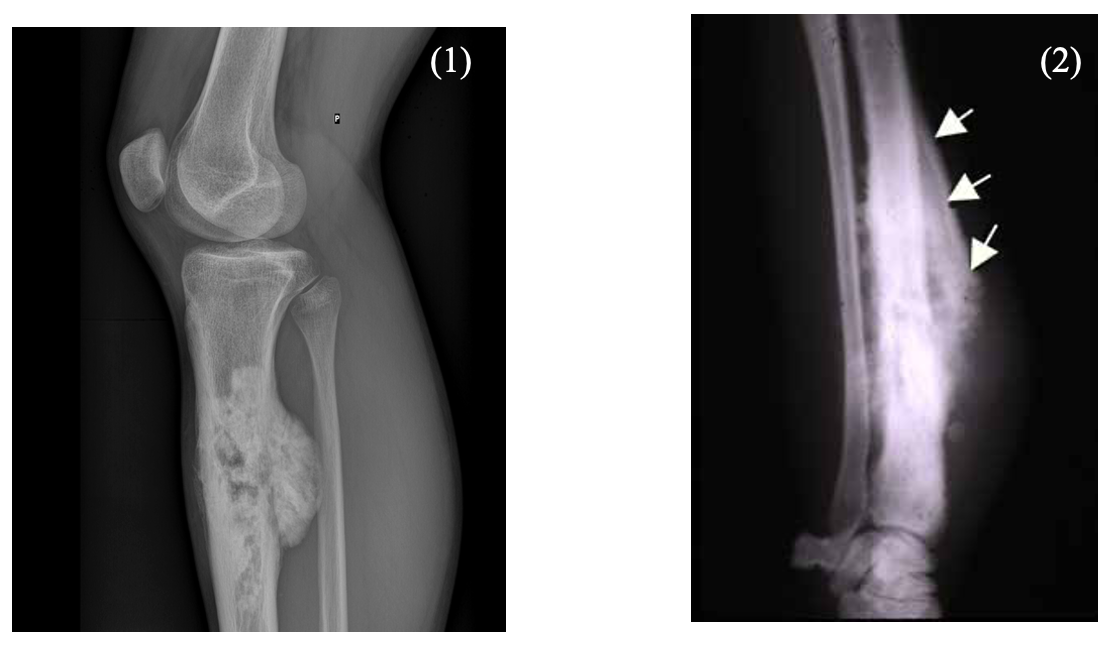

Ewing Sarcoma

This is a malignant proliferation of primitive cells which is seen in children and adolescents

– Unlike the osteosarcoma, this usually gives tumours in the middle of the long bones and pelvis

Unlike osteosarcoma, the tumour gives lytic (destroying bone lesions) which appear more lucent on x-ray

– X-rays show an onion skin appearance.

– If there a multiple lytic bone lesions, this produces a “moth eaten” pattern of disease

– Similar to the osteosarcoma, the inflammation also produces a periosteal reaction which may give rise to the Codman triangle finding on X-ray